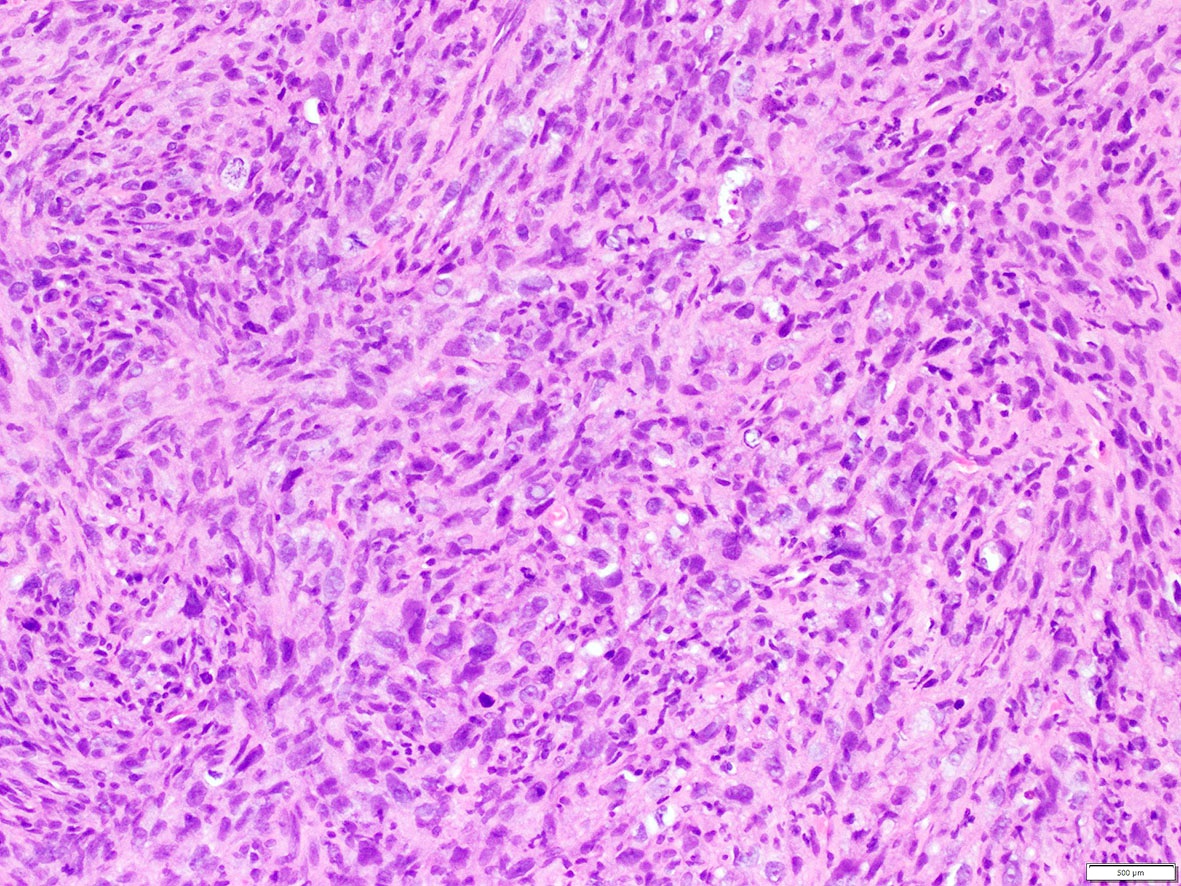

Microscopic (histologic) images

Contributed by A. Cristina Vargas, M.B.B.S., Ph.D., Patricia Guzman, M.D., Fiona Bonar, M.B.B.Ch., Alison Cheah, M.B.B.S. and Martin Jones, M.B.B.S.

Positive staining - disease

- ALK overexpression as a result of gene translocations / fusions:

- 50% of inflammatory myofibroblastic tumors (IMT) (Am J Surg Pathol 2015;39:957)

- Including the aggressive variant, epithelioid inflammatory myofibroblastic sarcoma (Am J Surg Pathol 2011;35:135)